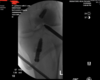

Surgical complication representing was a failure of hardware with resultant metal loose body in the joint identified. At the time of femoral reaming with a new a 10 mm low-profile reamer a piece of metal drill broke off. This was identified at the completion of reaming when we inspected the instruments. Per hospital protocol was brought in fluoroscopy we identified the metal fragment the posterior compartment of the knee. Was initially localized in the soft tissue the posterior aspect of the knee where I attempt to retrieve using anterior portals under direct visualization, then had to use the arthroscopy specifically a 70 degree scope posterior portal. Then made an accessory posterior medial portal and was able to excise the metal fragment. Used fluoroscopy to confirm fragment removal and notified the patient in the recovery room.

We did a root cause analysis for this complication and felt 1 contributing factor to improve upon is to ensure an ACL reconstructions revision where there may be previous tunnels to ensure we start the drill tip prior to contact with the bone. Moreover we are creating a standardization of reviewing instruments at th preoperatively the patient was consented for a block e completion of the case much like we do a needle and sponge.